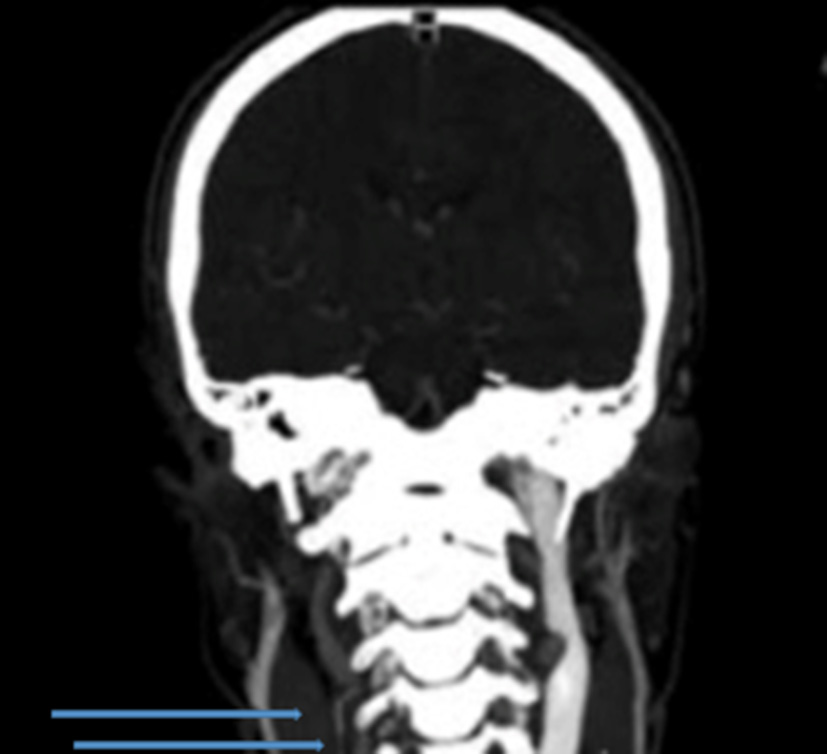

The ultrasound scan revealed an enlarged left internal jugular vein with a large collateral venous circle involving the superior thyroidal vein, ipsilateral external jugular vein, and vertebral vein; on the right side, only the vertebral vein was visible, and it appeared to be of increased size. Therefore, the hypothesis of hypoplasia or agenesis of the right internal jugular vein was suggested. The blood flow in those veins was regular, and there was no ultrasonographic evidence of other vascular diseases. An MRI of the head and neck confirmed the hypothesis of venous agenesis (Figure 2).

Figure 2

Magnetic resonance imaging with evidence of internal jugular agenesis.